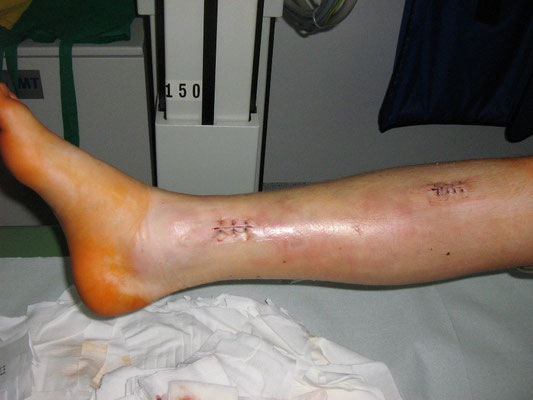

Stark verschobener Unterschenkelbruch bei einem 14- jährigen. Minimal-invasive Stabilisierung mit winkelstabiler Platte. Das Bein kann nach Abklingen der akuten Schwellung bereits wieder mit 15 kg an Gehstützen belastet werden. Volle Belastbarkeit nach 6 – 10 Wochen.